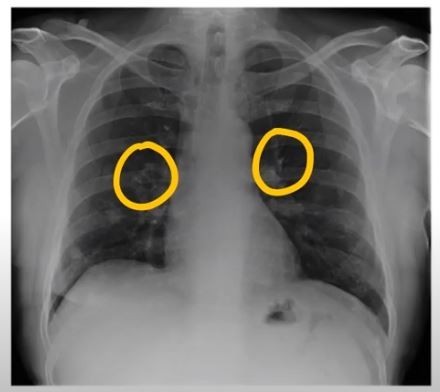

3. 숨 쉴 때 쌕쌕 거리는 소리가 난다.

보통 숨소리는 크게 들리지 않지만, 목이나 폐 부분에 뭐가 걸린 느낌이 나듯이 숨소리가 거칠어지는 걸 느낍니다.면 폐에 문제가 생겼을 확률이 높다. 꼭 내원해 엑스레이를 촬영해 보는 게 바람직합니다..